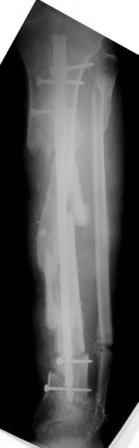

2) После репозиции более очевидна стала проблема дефекта кости в верхней трети голени, два фрагмента свободно лежат. Остановились на варианте перехода на интрамедуллярный синтез стержнем с покрытием костный цемент+ванкомимцин и замещении дефекта с помощью транспорта фрагмента (рис 2)

3) Третьим этапом наложили модуль на промежуточный фрагмент.(рис 3) И начали его транспорт на стержне в проксимальном направлении. (рис 3 а)